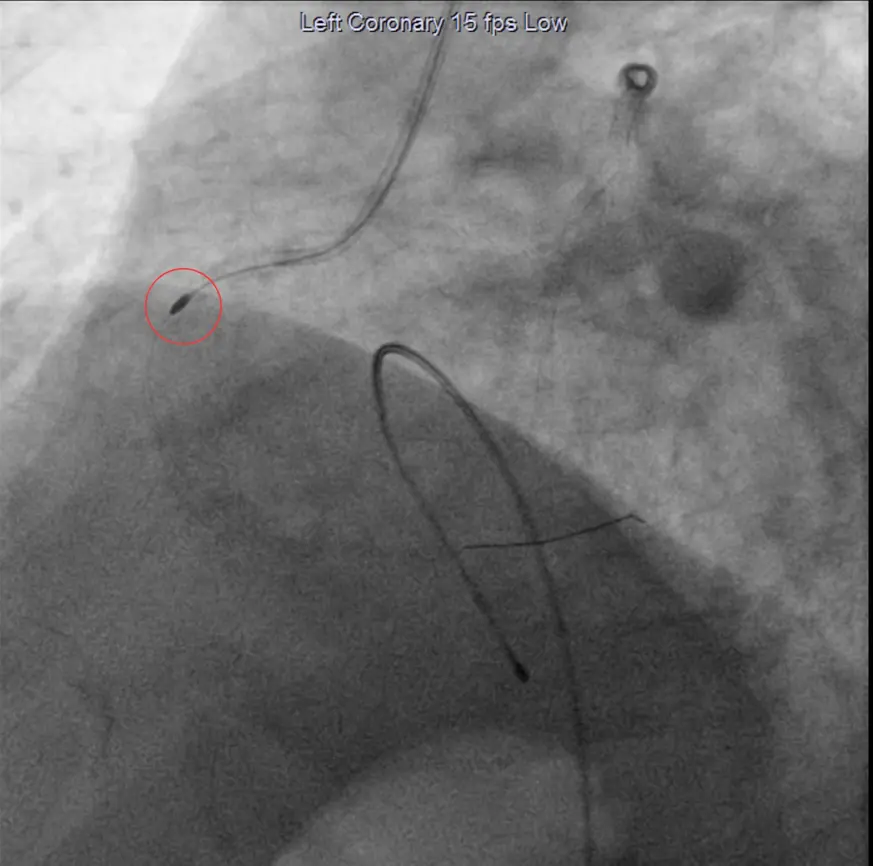

Tedavi hakkında bilgi veren Kardiyoloji Uzmanı Dr. İsmail Polat, “Bugün ikisi dış merkezden ikisi de direkt merkezimize başvuran dört hastamıza rotablatör cihazıyla rotablasyon işlemi yapacağız. Biz tıkalı damarları önce balon yapıyoruz, ardından stent takıyoruz. Bazı hastalarımıza maalesef bunları yapamıyoruz çünkü damarları çok kireçli ve çok sert oluyor. Bu hastalarda balon ve stenti geçirmek ve stenti optimal şartlarda açmak pek mümkün olmuyor. Bunlarda da şu an yeni bir teknoloji olan rotablasyon işlemi yapıyoruz. Rotablasyon işlemini rotablatör cihazı da yapıyoruz. Cihazın ucunda elmas tozu kaplı bir uç var. Kendi ekseninde dakikada 150 ile 200 bin devirle dönen cihazı tıpkı bir matkap gibi o kireçlenmiş, taşlaşmış olan o tıkalı damar bölgesine kasıktan iletiyoruz ve burayı traşlayarak bu kireçli alanı temizliyoruz. Ondan sonra balon ve stent işlemi yapıp hastayı bir gün koroner yoğun bakımda takip ettikten sonra ertesi gün taburcu ediyoruz” dedi.

Polat, “İşlem, anjiyografi laboratuvarında yapılmaktadır. Kasık veya kol damarınızdan işlem yapılabilir. Bu damarlara yerleştirilen kılıflar içerisinden kalp damarlarınıza plastik borular (kateter) yerleştirilir. Bu plastik borular yardımı ile ilgili darlığa rotablatör cihazı ilerletilir. Tıraşlama işlemi sırasında ve sonrasında normal anjiyografi uygulanarak darlığın durumu ve değişiklikler ayrıca incelenir” diye konuştu.